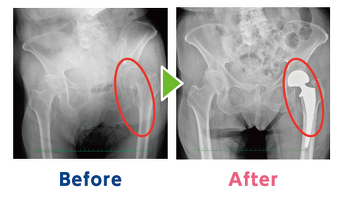

③早期治療で自分らしい生活を取り戻そう 高齢者の骨折治療

②早期治療で自分らしい生活を取り戻そう 高齢者の骨折治療

①早期治療で自分らしい生活を取り戻そう 高齢者の骨折治療